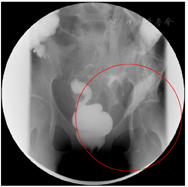

实验室检查:白细胞计数9.2×109/ L,中性粒细胞88.3%,血红蛋白56 g/L,降钙素原124 μg/L,白蛋白22.1 g/L,前白蛋白20 mg/L。消化道道造影提示,经肛门注入造影剂,可见只有直肠中下段显影良好其余结肠显示不清,广泛结肠及直肠炎,回盲部也受累(图1)。经外瘘口注入造影剂,见左盆腔不规则脓腔显影(图2)。骨密度检测提示骨质疏松。